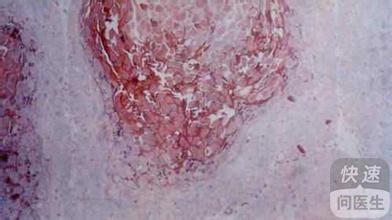

皮肤隧道(隧道样丘疹)

这是疥疮最具特征性的表现,疥螨在皮肤表层挖出细小的隧道,通常呈灰白色或浅棕色,长度约2-10毫米,常见于手指缝、指甲周围、手腕和肘部,隧道内常伴有细小的丘疹或水疱,抓挠后可能破裂,形成轻微糜烂面。图片描述:一张放大后的皮肤隧道图,隧道像笔迹一样细,周围皮肤略微发红,隧道内可见疥螨爬行的痕迹。